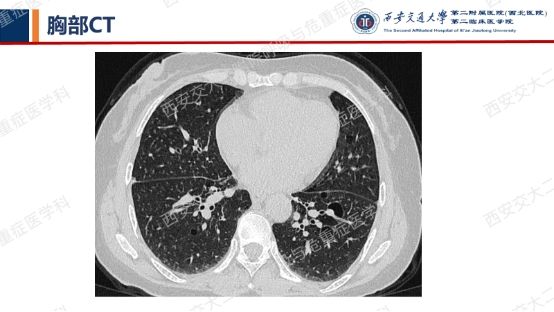

患者呼吸道症状并无太多特异性,还是从影像资料入手,右肺中叶外侧段高密度灶并纵隔及右肺门淋巴结肿大,同时存在双肺多发囊性病变,一元论?多元论?

囊性病变常要鉴别的疾病包括我们第一期的BHDLAM,还有LIP(淋巴细胞性间质性肺炎)、PLCH(肺朗格汉斯组织细胞增多症)、PLCDD(肺轻链沉积病)等。该患者囊性病变特点:沿支气管血管束周围分布,多个囊有血管贴边或穿行于囊肿壁。追问患者有口干不适,进一步行SS-A 52 101.65 AUSS-A 60 47.30AUANA 阳性(+),滴度1:10000 阳性(+),又经唾液流率、泪液流率、唇腺活检及风湿免疫科会诊,诊断干燥综合征。

需要强调的是,LIP影像表现较为复杂——弥漫性GGO+边界模糊之小叶中心性结节+胸膜下结节+支气管血管束增粗+多发囊样气腔各种征象可单独或同时存在。我们最近几期病例会聚焦在弥漫性囊性肺疾病,所以展示的病例影像基本以囊变为主。